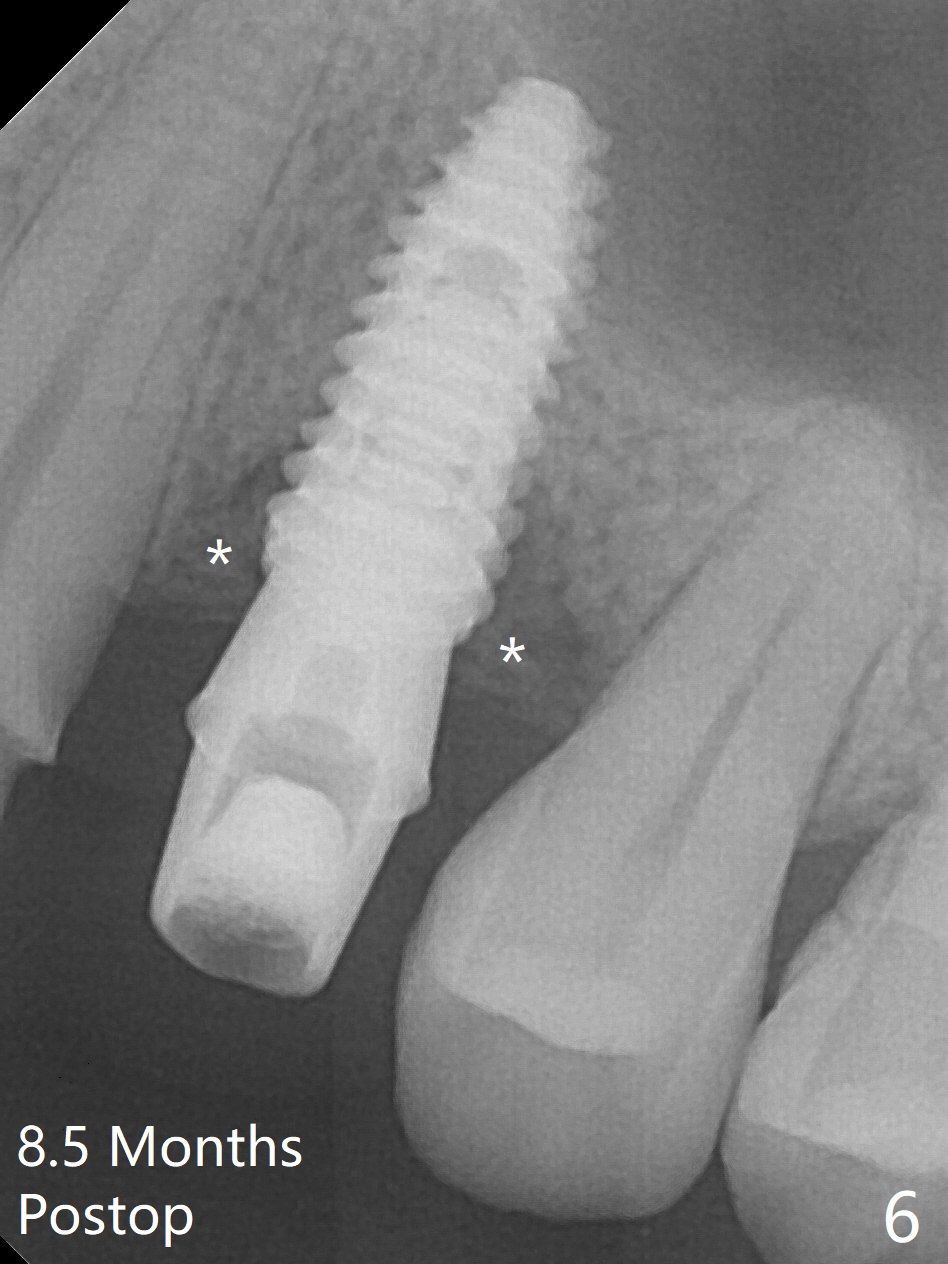

After extraction of the residual roots at #12 and crown prep at #11, osteotomy at #12 is established with Pointed Lindamann bur and 2.2 mm bur for ~ 15 mm. There feels to be sinus floor perforation; a parallel pin is inserted deeper than expected (Fig.1), but there is no membrane perforation. Following sequential osteotomy, a 4x10 mm dummy implant is placed partially with stability (Fig.2). When the same sized definitive implant is placed subcrestally (Fig.3-5 (*: Vera Graft)), the stability remains (~60 Ncm) in spite of the fact that the trajectory is changed once. The coronal socket does not seem to heal 8.5 months postop, in part due to poor hygiene of splinted provisional (Fig.6).